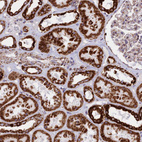

Immunohistochemical staining of human skeletal muscle shows strong granular cytoplasmic positivity in myocytes.